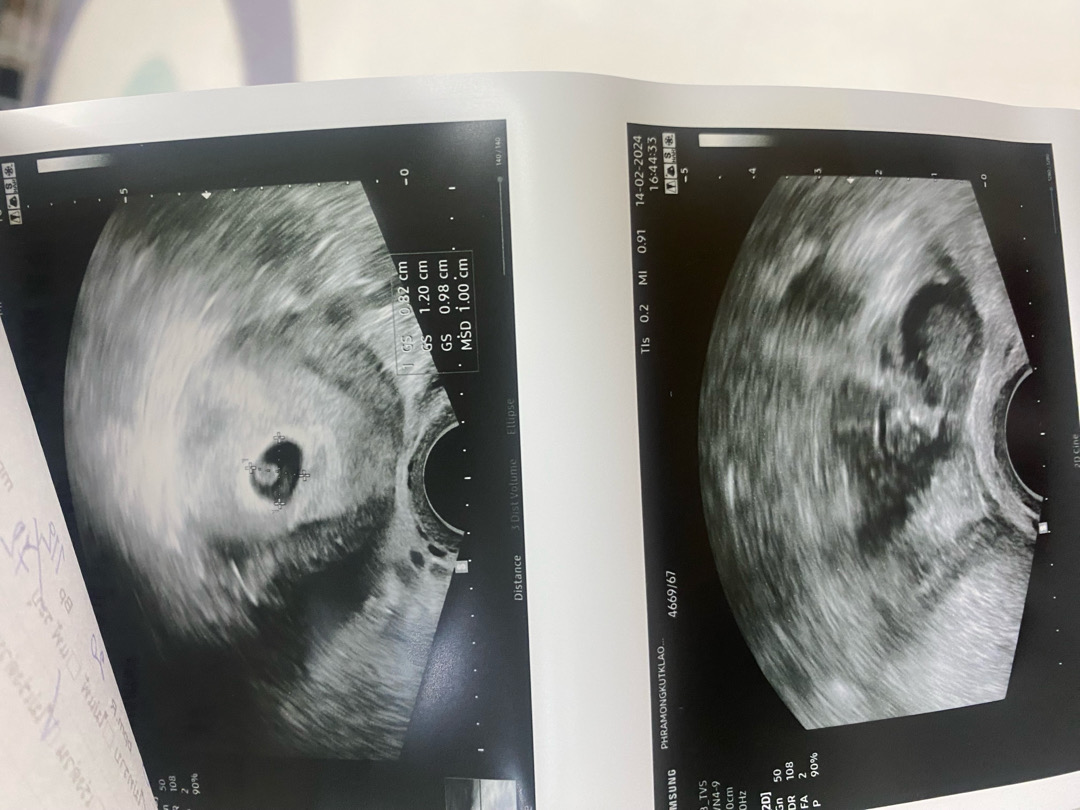

ไปตรวจรพ.นอกเวลามาค่ะ หมอคนละคนกับที่นัดอีก 2 วัน เจอถุงตั้งครรภ์และไข่แดง แต่หมอบอกว่ายังบอกไม่ได้ว่าตั้งครรภ์มั้ยเพราะยังไม่มีตัวน้อง อีกสองอาทิตย์มาตรวจใหม่ถ้าเจอตัวแล้วค่อยฝากครรภ์ หรือควรฝากเลยดีคะ

เราตรวจเลือดเจอฮอร์โมนตั้งครรภ์ต่ำๆ เลยค่ะ หมอบอกเพิ่งติดเลย แต่พอซาวด์เห็นถุงไข่แดงแล้วก็ยังไม่บอกว่ากี่อาทิตย์เลยงงๆ ค่ะ 😅😅